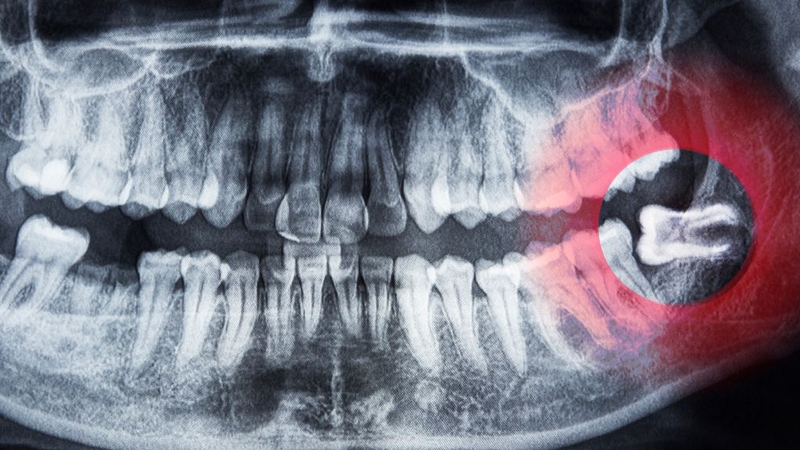

Nhổ răng khôn có đau không?

Nhổ răng khôn chắc chắn sẽ gây đau, nhưng cơn đau không giống nhau ở mọi người và có thể được kiểm soát tốt nếu thực hiện đúng cách. Trong quá trình nhổ, bệnh nhân được tiêm thuốc tê nên gần như không cảm nhận cơn đau. Thay vào đó, bạn chỉ thấy vùng nướu tê cứng, đôi khi có cảm giác căng tức hoặc nghe tiếng tác động của dụng cụ nha khoa. Điều này thường không quá khó chịu và hoàn toàn có thể chịu đựng được.

Nhổ răng khôn có đau không được nhiều người lo lắng thắc mắc

Sau khi thuốc tê hết tác dụng, cảm giác đau nhức sẽ xuất hiện. Mức độ đau phụ thuộc vào độ khó của ca nhổ, chẳng hạn răng mọc thẳng thường ít đau hơn răng mọc lệch hoặc mọc ngầm. Ngoài ra, tay nghề của bác sĩ và khả năng hồi phục của mỗi người cũng ảnh hưởng đến mức độ khó chịu sau nhổ. Đối với đa số trường hợp, cơn đau thường rõ nhất trong 1 - 3 ngày đầu, sau đó giảm dần và biến mất hẳn sau 1 - 2 tuần.

Tóm lại nhổ răng khôn có đau không? Có nhưng cơn đau hoàn toàn có thể kiểm soát nhờ thuốc giảm đau, kháng viêm và cách chăm sóc khoa học. Vì vậy, bạn không nên quá lo lắng hay trì hoãn việc nhổ răng khôn khi đã có chỉ định. Bởi sự chần chừ đôi khi sẽ khiến tình trạng răng miệng trở nên phức tạp và gây đau đớn hơn khi điều trị.